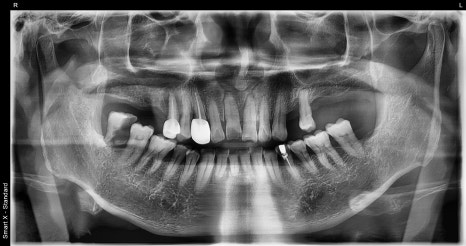

초진 시 촬영한 전체 파노라마 X-ray 사진

환자분은 고혈압과 고지혈증을 가지고 계셨기 때문에,

수술 및 치료 시 출혈, 감염 위험 등을 세심하게 고려해야 했습니다.

서울대병원 응급실 경험을 바탕으로, 전신질환을 고려한 안전한 외상 처치를 진행했습니다.